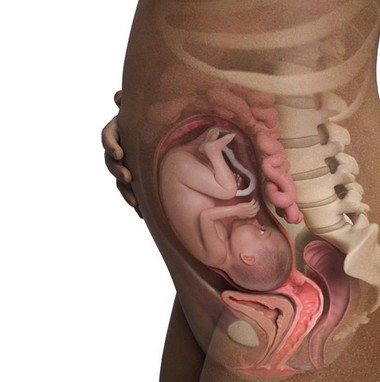

مراحل نمو الجنين بالصور

مراحل نمو الجنين بالصور ، بالطبع لا يمكن أن ننكر مدى الفرحة والسعادة التي يشعر بها الوالدان عند سماع خبر الحمل فتبدأ المرأة بتصور هذه القطعة التي تنمو في احشائها وتكبر يوماً بعد الآخر، ويبدأ الجنين بالنمو على مجموعة من المراحل في مجموعة من الشهور والأسابيع فإذا كانت لديك الرغبة في التعرف على هذه المراحل سيكون هذا المقال مرجع رائع لديك من دار الطب يعرفك بالتفصيل على مراحل نمو الجنين بالصور .

خلال هذا الأسبوع يبدأ شكل الجنين بالوضوح ويصبح قريباً للشكل الذي يظهر به الجنين عند الولادة، ولكن مع اختلاف أنه صغير الحجم كما أ هناك بعض الأعضاء لم يكتمل نموها بعد مثل الرئتين والكبد، جدير بالذكر أن هناك حالات معينة يولد فيها الطفل خلال هذا الأسبوع ويعيش بشكل طبيعي جداً إذا تم الاهتمام والعناية به من قبل الأطباء بعد ولادته.

خلال هذا الأسبوع يبدأ موعد الولادة بالاقتراب ويبدأ رأس الجنين بالنزلاق تجاه منطقة الحوض وبالطبع يجب المتابعة مع الطبيب المختص خلال هذه الفترة لمعرفة آخر التطورات.

هذا الأسبوع هو الأسبوع الذي يفترض أن تتم فيه الولادة ويكون حجم الجنين خلاله 50 سم ووزنه حوالي 2900 جم ويختلف الأحجام بفروقات بسيطة من جنين لآخر ولكن المشترك في الموضوع أن أجهزة الجسم اكتملت وأصبحت تعمل بصورة سليمة لا تؤثر على حياة الطفل بعد ولادته.